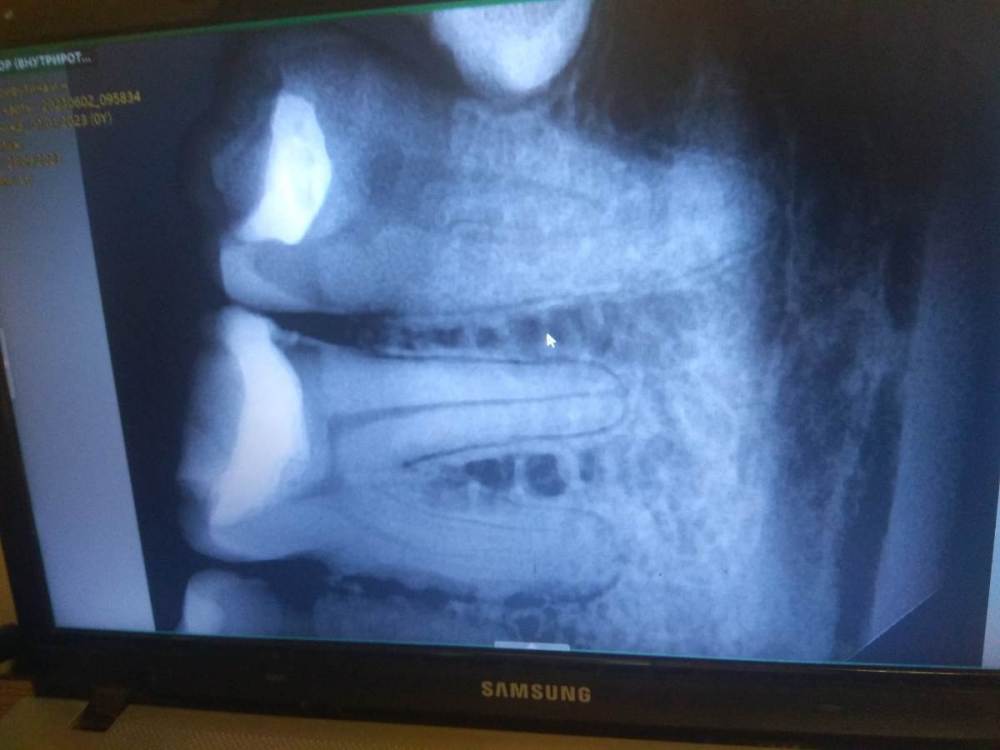

Primavera2023 Опубликовано 2 ноября, 2023 Поделиться Опубликовано 2 ноября, 2023 (изменено) Здравствуйте. Мне 32 года. В конце сентября стал побаливать зуб 3.6. боль была несильная, но регулярная, особенно как реакция на холодное. На зубе уже 7 лет стояла большая пломба. Я пошла к стоматологу, у которого лечилась ранее, и мне обнаружили небольшой кариес сбоку на мезиальной поверхности. Но запись была на 2 месяца вперёд. Я пошла к другому стоматологу. Он поменял старую пломбу, а новый кариес не заметил, как я не говорила. Там была маленькая дырочка на границе десны. От неё шла эта боль. А когда он менял пломбу было совсем почти не больно. До пульпы осталась тоненькая стеночка дентина. Сразу поставил постоянную пломбу, сказал не будет ставить временную. Через несколько дней зуб стал уже ощутимо болеть, боль усиливалась ночью, была пульсирующей. Я пошла к третьему стоматологу, где мне удалили нерв. В процессе пломбировки 3 корневых каналов стоматолог вывел в одном материал за апекс на 3-4 мм вместе с гуттаперчевым штифтом. Канал распломбировали, гуттаперчу достали, а силер АН + нет. После этого стало очень больно накусывать на зуб и боли не проходят уже неделю. Тогда же стоматолог наконец заметил кариес по границе десны. Теперь ещё одну стенку зуба сказал надо убирать. Во вторник будет завершение лечения с установкой титанового штифта. Может не стоит торопиться и подождать ещё неделю, а если боль не пройдёт, проще удалить этот зуб? Денег уже потратила немало, а я получаю МРОТ. Может соседняя 7 встанет со временем на место 6, если ту удалить, а там и дистопированная 8 подтянется? Рентгена после пломбировки каналов сейчас на руках нет. Возьму в следующее посещение. На первом снимке зуб до депульпации после замены пломбы. На втором зуб еще со старой пломбой. (в конце сентября). Изменено 2 ноября, 2023 пользователем Primavera2023 Ссылка на комментарий